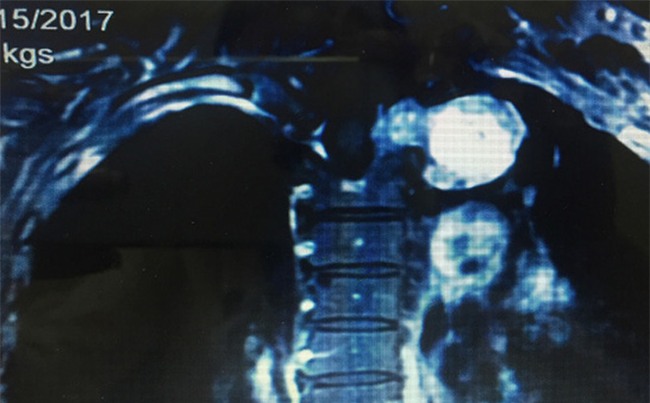

Hình ảnh khối u phình to trong tuỷ sống, chèn ép vào lồng ngực

Khi chụp cộng hưởng từ, BS phát hiện có khối u từ trong ống sống ngực phát triển xâm lấn vào trong lồng ngực, khối u kích thước lớn 6x5cm.

Khối u lớn ăn sát vào hõm đỉnh lồng ngực, đè đẩy vào bó mạch thần kinh cánh tay, đặc biệt là tĩnh mạch dưới đòn trái khiến bệnh nhân đau nhức. Bệnh nhân được chẩn đoán là u thần kinh tủy sống, chỉ định phẫu thuật.